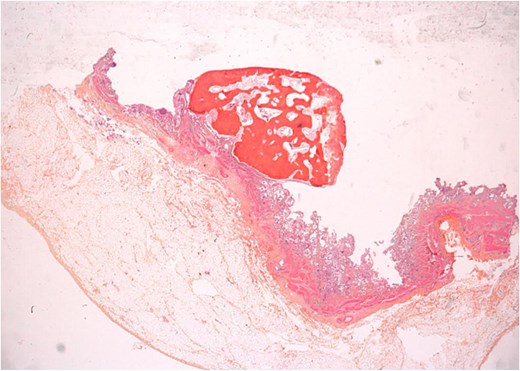

An urgent laparoscopic cholecystectomy was performed. However, upon histopathological analysis of the removed gallbladder (Fig. 2), bone metaplasia was identified in the gallbladder wall (Fig. 3). This finding was unexpected, although similar cases have been reported in the literature in the context of chronic gallbladder conditions.

Microscopic image showing bone metaplasia in the gallbladder wall.